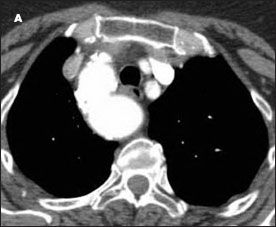

A high-resolution CT scan of the chest confirmed a right-sided aortic arch; a small ductus diverticulum was also noted just distal to the origin of the left subclavian artery, which was causing near circumferential compression of the trachea (Figure 2). Tracheal diameter at the thoracic inlet measured 1.1 cm, whereas maximal tracheal width at the level of greatest narrowing was 4 mm. Tracheal stenosis was strongly suspected.

Figure 2 – A highresolution CT scan of the chest confirmed the finding of a right-sided aortic arch and revealed marked narrowing of the trachea (B, yellow arrow) and a fibrous band between the left subclavian artery and the descending aorta (B, white arrow). The tracheal narrowing was apparent when comparing the view at the level of stenosis (B) with the cephalad (A) and caudad (C) views.